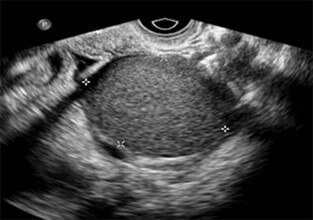

Transvaginal Ultrasound (TVUS)

Transvaginal ultrasound is the gold standard initial imaging modality for evaluating ovarian cystic masses.

Common Ultrasound Patterns

• Endometrioma: Homogeneous "ground-glass" appearance